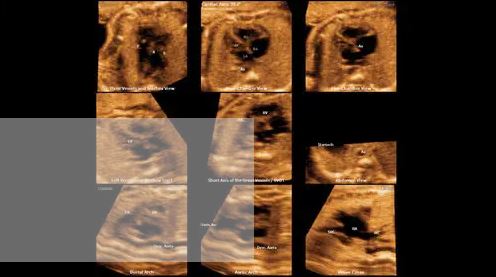

Modes d’imagerie: noir et blanc, doppler couleur, 3D/4D

– CrystalBeam™ est une nouvelle technologie de formation de faisceau bénéfique pour offrir une résolution d’image de haute qualité, et une uniformité accrue des images.

Une nouvelle formation de faisceau pour une création d’image en profondeur: CrystalBeam™ utilise les technologies Arbitrary Waveform Transmission, Massive Parallel Beamforming et Synthetic Aperture pour produire une fréquence d’images plus rapide et une meilleure uniformité de l’image.

Images 2D sophistiquées traitées par CrystalLive™: CrystalLive™ vous aide à poser des diagnostics plus sûrs grâce à des images 2D fondamentales. Parmi les principaux avantages des images 2D, citons les images supprimées des ombres, les artefacts de halo atténués et les zones floues atténuées.